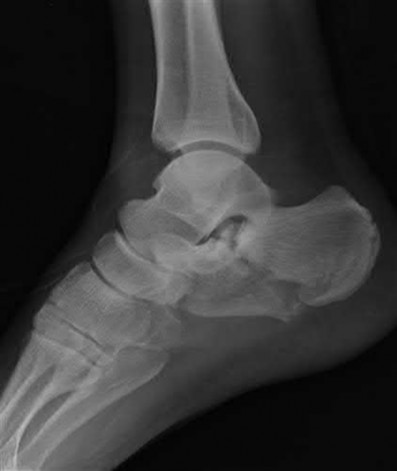

A 38-year-old male suffers the injury shown in Figure A. During operative fixation, free osteoarticular fragments are encountered and reconstruction of these pieces is attempted. Postoperatively, which of the following will have the most beneficial effect on the healing potential of the surviving chondrocytes within these reconstructed articular segments?

Figure A demonstrates a comminuted tibial plateau fracture with significant intra-articular involvement. Basic science evidence has demonstrated that post-operative gentle compressive loading may have a positive impact on articular cartilage healing; however, excessive shear loading may be detrimental.

Irrgang et al provide guidelines for rehabilitation following surgical management of articular cartilage lesions of the knee. They state that after articular cartilage repair, exercises to enhance muscle function must be done in a manner which minimizes shear loading of the joint surfaces in the area of the lesion. The authors also discuss the benefits of gentle compressive loading and motion of the joint, and its positive effects on chondrocyte nutrition.

Furthermore, they recommend a period of protected weight bearing as often being necessary, and that this should be followed by progressive loading of the joint.

Illustration A is a diagram showing the different layers of joint cartilage.